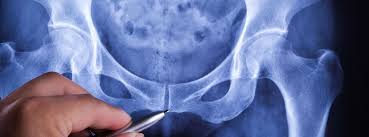

El suelo pélvico es un conjunto de músculos y tejidos ubicados en la base de la pelvis, que tienen una importante función en el control de la vejiga, el útero y el recto, pero con el paso del tiempo, es posible que se distienda, creando situaciones que pueden afectar a la salud.